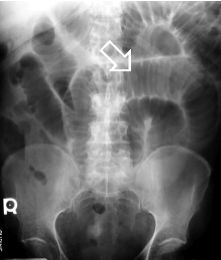

Small bowel loops contain transverse folds known as valvulae conniventes or plica circularis. These folds are well seen in this patient with small bowel obstruction. Usually the colon is decompressed and hardly visible (fig. 20).

Figure 20 – Plica circularis